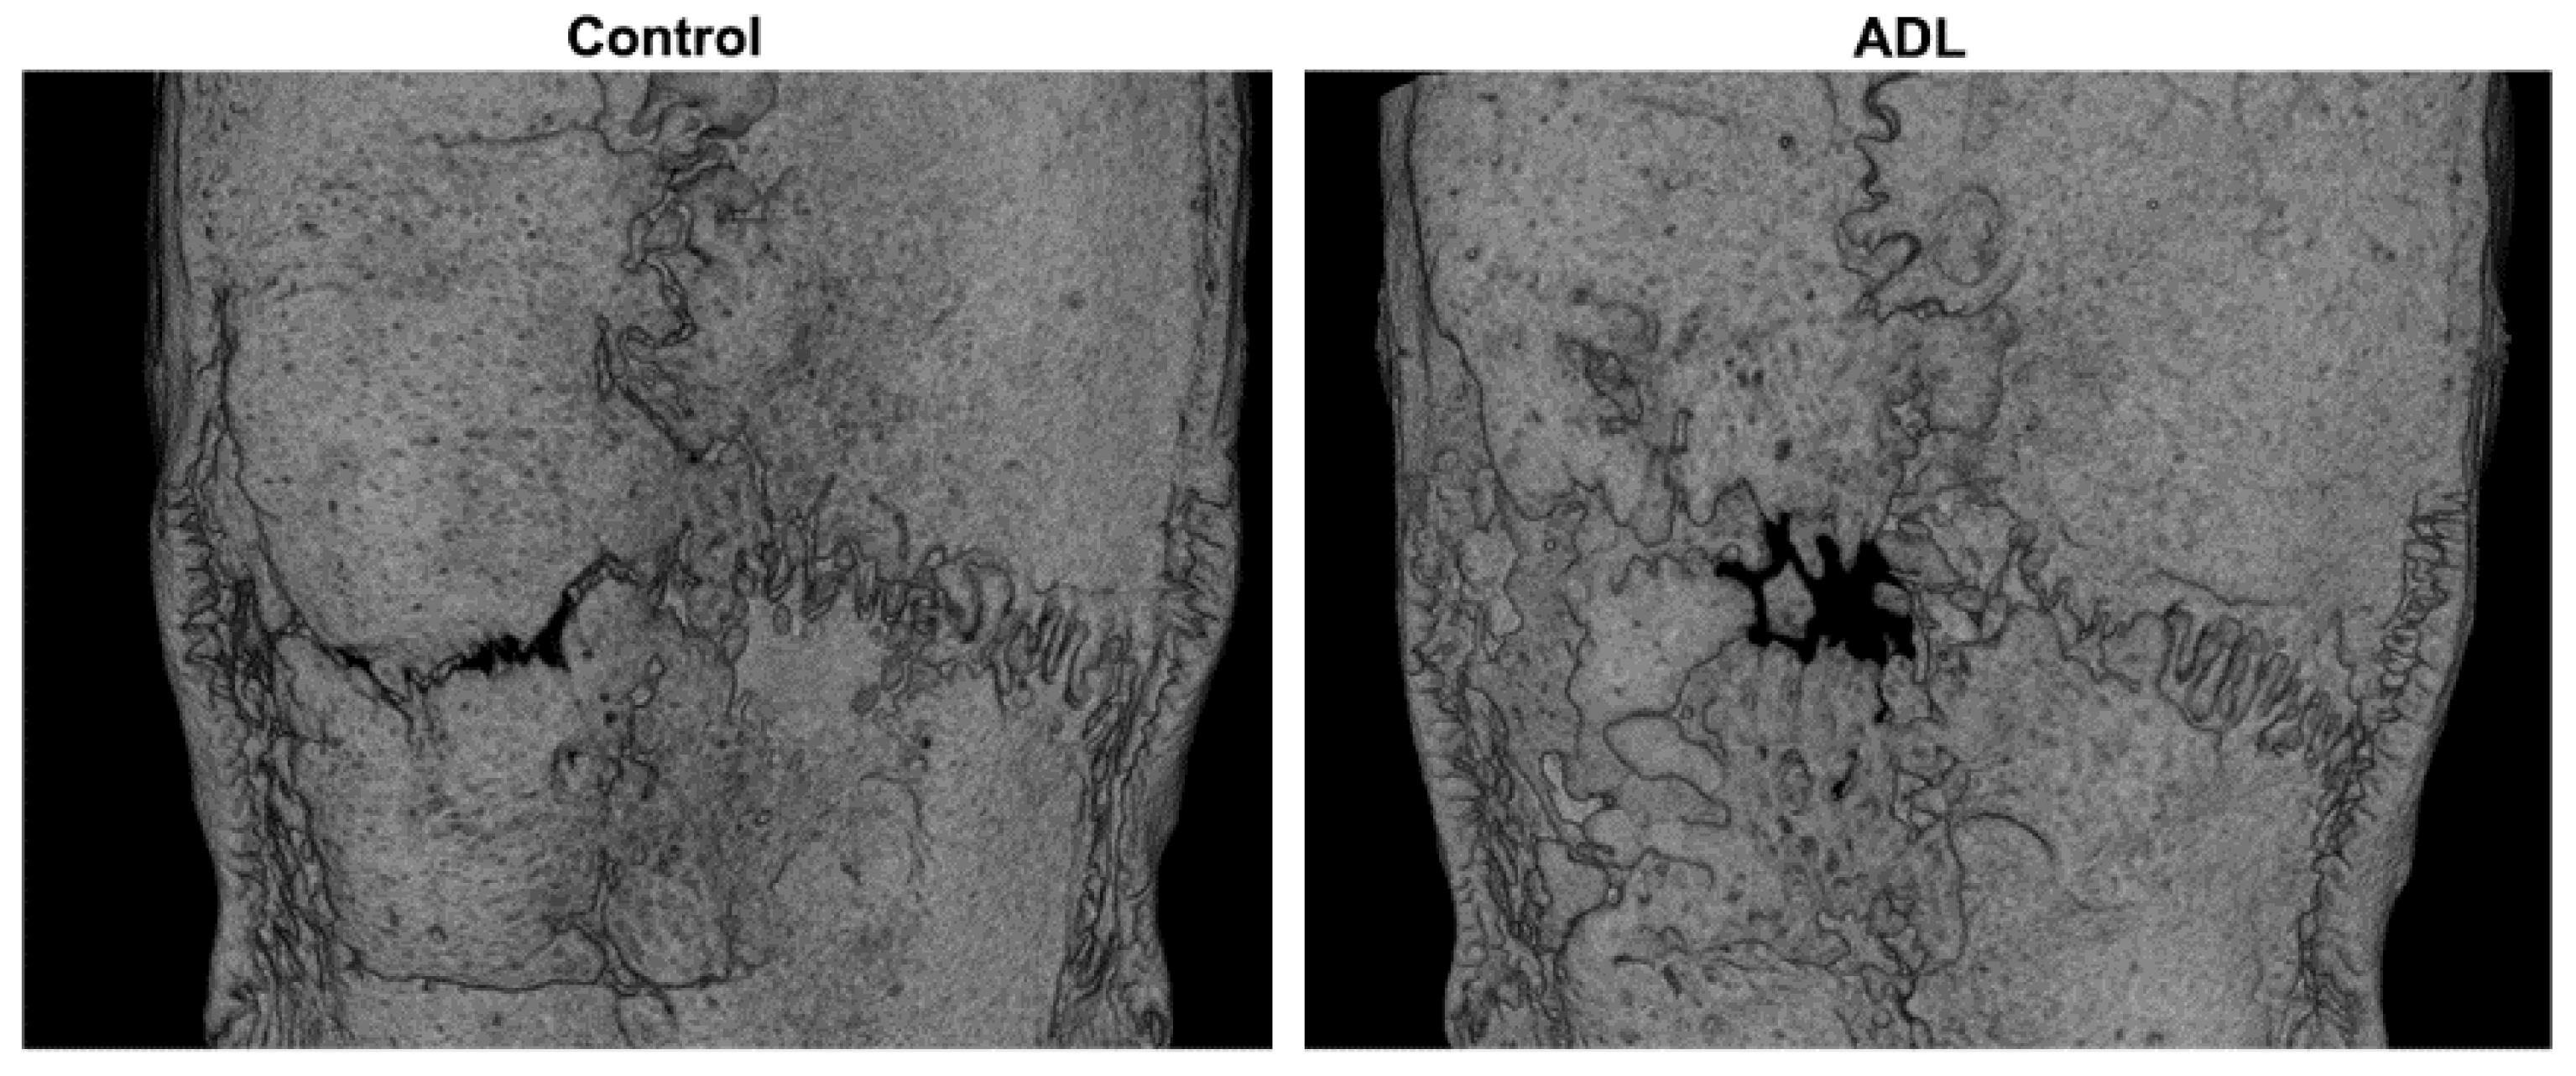

3.2. µCT Analysis